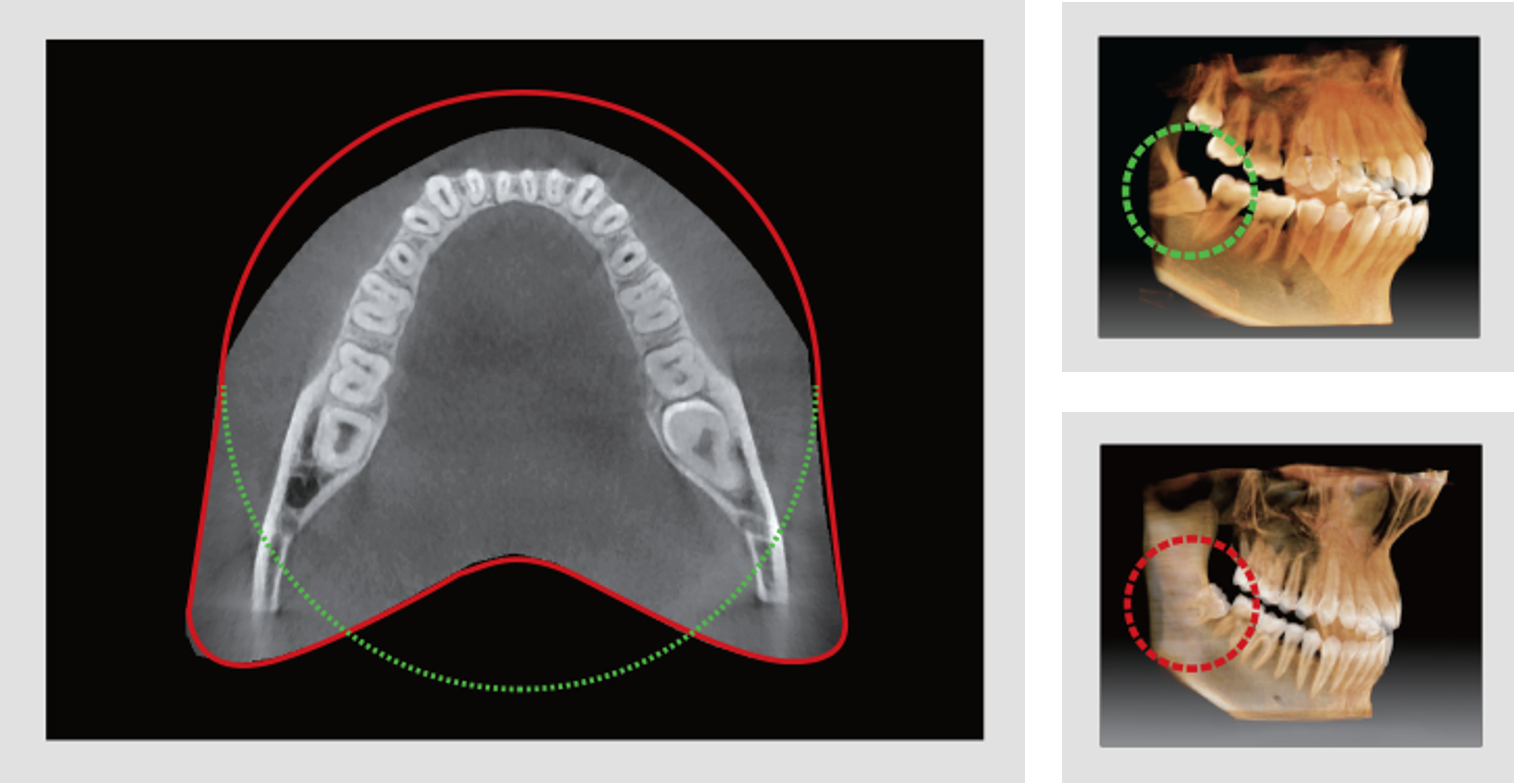

FOV DE ARCO EXTENDIDO

El innovador FOV de Smart Plus proporciona un volumen en forma de arco, que muestra una vista más amplia de la dentición en comparación con otros dispositivos del mismo campo de visión. Para los terceros molares, existe una alta posibilidad de que el diente se corte de la imagen. El “FOV de arco extendido” elimina esta posibilidad y proporciona al médico toda la dentición necesaria para un diagnóstico completo.